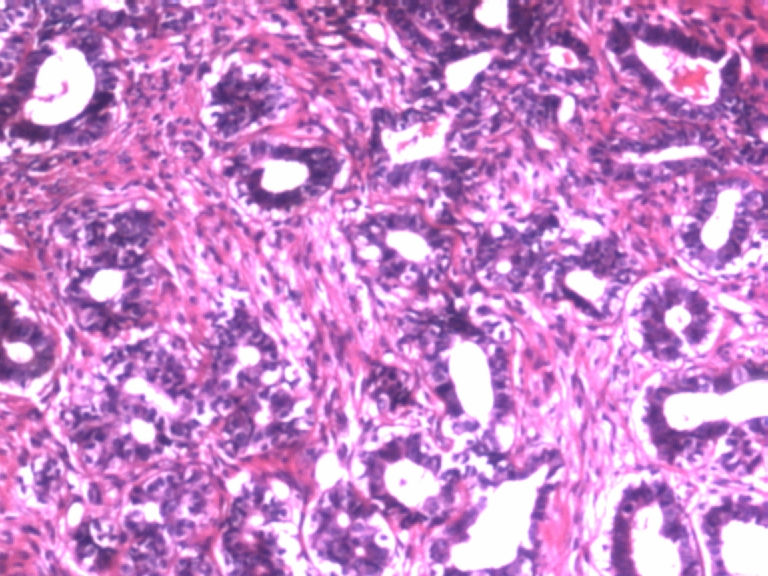

• 乳腺肿物图4

图4

患者,女,29岁,右侧乳腺肿物一个月。切面淡黄,均匀一致,质中。

标签:乳腺管状腺瘤

病变组织小叶结构未见,见管状、盲管状的腺管,周围似有空亮的肌上皮,腺上皮可见细小的核仁,染色质均细,导管上皮普通型增生。有包膜为盲管状腺瘤,则为腺病。

本例似乎有肌上皮存在,那就可能是良性的,如果有包膜就是腺瘤,管状腺瘤。